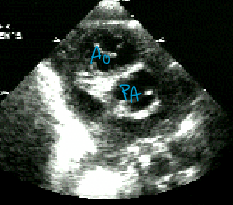

Your patient has d-TGA with complete transposition of the great arteries. Describe the appearance of PSSAX.

Aortic valve is anterior and rightward of the PV because the Ao comes off the RV.

Describe the findings of this image.

PSSAX with the aorta anterior and rightward of the PV.

Indicates complete transposition of the great arteries.

Don’t know if d-TGA or l-TGA.